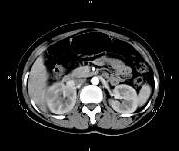

问题 女,27岁,寒战高热、尿频、尿痛3天,尿检:白细胞(+++),CT平扫及增强扫描如图所示,下列说法错误的是 ( )

选项 A、考虑为急性肾盂肾炎 B、考虑为慢性肾盂肾炎 C、增强后可见条片状密度减低区 D、左肾未见异常 E、右肾体积增大

答案 B